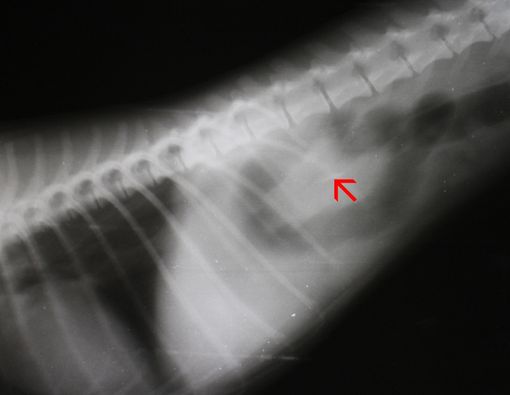

Corpus alienum sendiri artinya menurut dr. Devia Irine Putri adalah benda asing. Benda-benda asing memang diketahui bisa masuk ke dalam tubuh lewat berbagai mekanisme.

Jadi, jangan heran kalau ada benda dalam tubuh saat pemeriksaan radiologi. Contohnya, kerap terlihat benda-benda kecil dalam tubuh. Kalau benda tersebut tidak mengganggu, maka terbilang aman dan bukan masalah besar.

Namun, baru dinyatakan bermasalah kalau sudah sampai mengganggu kehidupan sehari-hari.

"Iya benar [kerap disebut susuk]. Semua benda asing yang di dalam tubuh disebut corpal. Misalnya ada serpihan besi di mata, itu corpal di mata. Biji kacang hijau di hidung, maka itu corpal di hidung," kata dr. Devia Irine.

"Susuk sendiri dalam dunia medis juga bisa disebut corpal, karena tidak seharusnya berada dalam tubuh," sambungnya.

Namun, dunia medis memang tidak mengenal susuk atau kemasukan benda asing secara tidak sengaja. Semua benda asing yang masuk ke tubuh dianggap sebagai corpal.